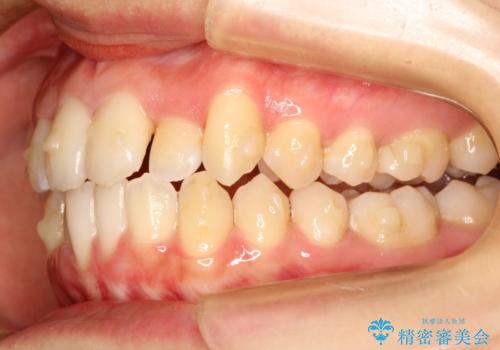

初診時の歯並びの状態としては、上下ともに全体に及ぶの中等度以上のがたつき(叢生)があり、前歯数本が反対交合の状態でした。

強い叢生がありましたが、抜歯は行わず上下顎ともに、主に歯列弓の拡大とディスキング(歯と歯の間に隙間を作る処置)を行い叢生を改善しました。